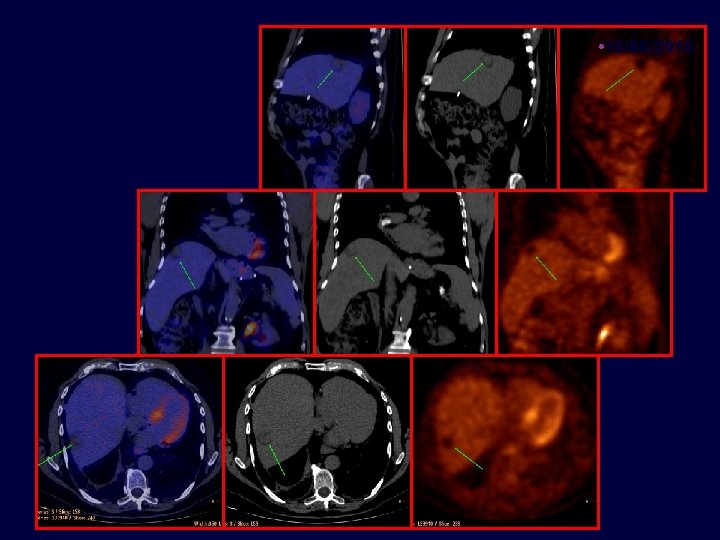

• Caso clínico • Paciente de 71 años con cáncer de colon estadío III en 07/2004, Metástasis hepáticas en 06/2008 • 65 años, enfermedad coronariana, médico. Resección carcinoma de colon T 3 N 1 M 0 • 07/2004 • Termina FOLFOX x 12 03/2005 06/2008 11/2008 06/2010 • - Lesiones hepáticas – ambos lóbulos

• 06/2008